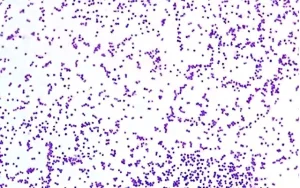

Staphylococcus aureus, insanlarda ve hayvanlarda enfeksiyonlara neden olabilen Gram-pozitif bir bakteridir. Yuvarlak şekilli (kok) ve üzüm salkımı görünümünde mikroskop altında gözlemlenen bu bakteri, hem kommensal (zararsız) olarak hem de patojenik (hastalık yapıcı) olarak vücutta bulunabilir. En yaygın olarak cilt ve mukozalarda yerleşim gösterir ve fırsatçı patojen olarak enfeksiyonlara neden olabilir.**